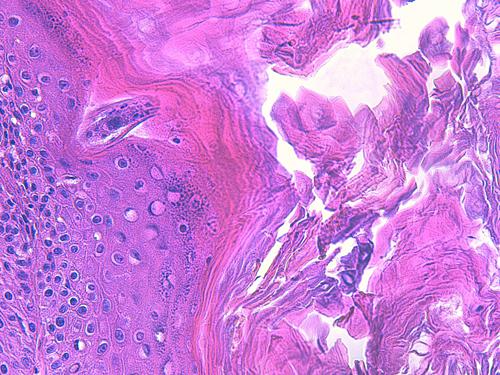

On observe une hyperplasie de l’épiderme et de la gaine épithéliale folliculaire externe en région infundibulaire, hyperplasie irrégulière associée à une alternance d’ortho et de parakératose. Les abouchements folliculaires sont dilatés, obstrués d’un matériel kératosique et pustulo-croûteux, les pustules étant riches en éosinophiles (Photo 1,2,3,4,5,6). On peut observer, au sein de l’épiderme et des abouchements folliculaires, des lésions pustuleuses dessinant de petits trajets entourés de structures épithéliales fissurées avec rupture des desmosomes intercellulaires avec un aspect focalement nécrolytique (Photo 4,7,8,9,10,11,12).

Photo 3 (Hémalun-Eosine X100) peau velue : Les infundibula folliculaires sont le siège d’une acanthose irrégulière et d’une hyperkératose (avec alternance d’ortho et de parakératose). Leur abouchement est souvent obstrué d’un matériel pustuleux. Leur gaine épithéliale externe présente des lignes de fissuration et de lyse des attaches desmosomiales des cellules épithéliales, dans lesquelles s’immiscent des granulocytes.

Légendes de la Photo 3 :

- Double flèche bleue pointillée : grand axe des infundibula folliculaires

- Ovales jaunes : pustules obstruant l’ostium ou l’infundibulum

- Flèches jaunes : fissuration linéaire dans la gaine épithélilae externe d’un follicule parallèle au grand axe de l’infundibulum

- Étoiles vertes évidées : hyperkératose orthokératosique

- Étoiles rouges pleines : hyperkératose parakératosique

- Étoiles turquoises pleines : infiltrat inflammatoire dermique périvasculaire à diffus

Photo 4 (Hémalun-Eosine X200) peau velue : Vue rapprochée de la Photo 3 montrant

la zone de fissuration de la gaine épithéliale externe d’un infundibula folliculaire avec lyse des

attaches desmosomiales intercellulaires et afflux de granulocytes éosinophiles donnant

naissance à des micro-pustules pariétales multiloculaires.

Légendes de la Photo 4 :

- Double flèche verte : grand axe de l’infundibulum folliculaire

- Double flèche rose : épiderme

- Flèches jaunes : fissuration de la gaine épithéliale externe avec lyse des attaches desmosomiales intercellulaires et afflux de granulocytes éosinophiles

- Ronds marrons : parakératose

- Étoiles rouges : micro-pustules pariétales multiloculaires (folliculite murale) et luminales obstruant l’abouchement folliculaire

- Étoiles turquoises : à gauche infiltrat inflammatoire dermique (au milieu en bas, erreur)

- Étoile vertes : orthokératose